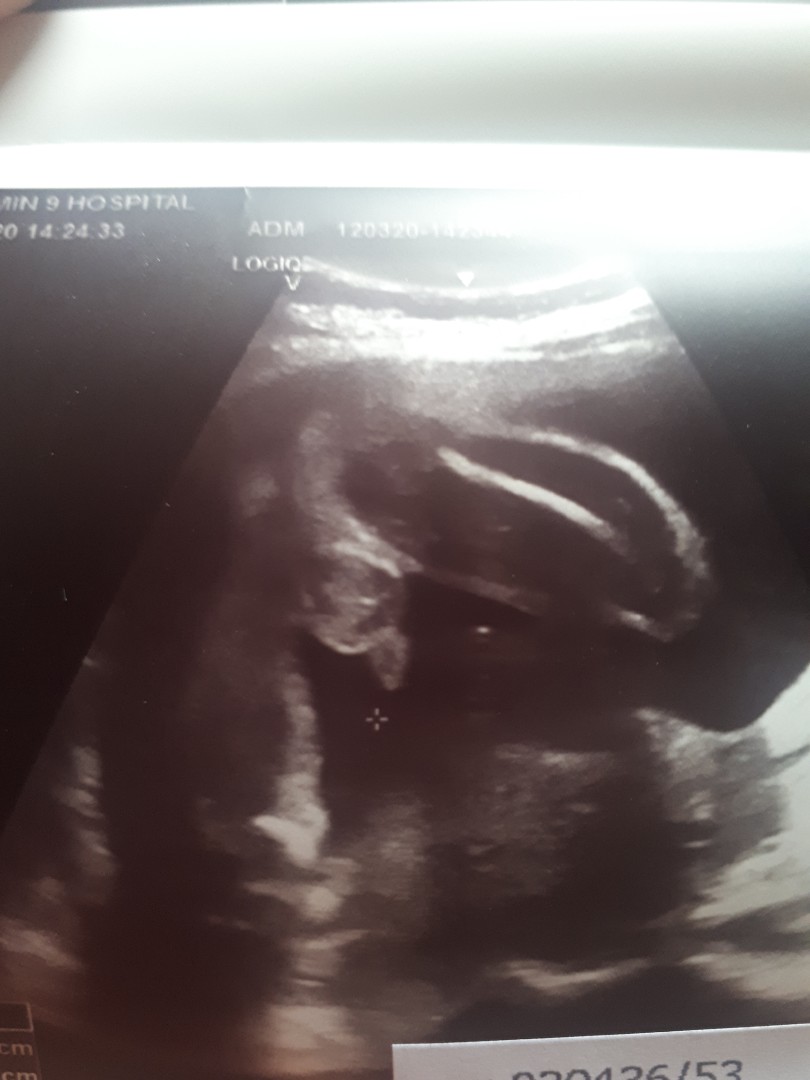

ในภาพเป็น ผช ใช่ไหมค่ะ พอดีหมอขอชัวร์ๆ เดือนหน้า เลยสอบถามแม่ๆ ที่มีประสบการณ์ลูกชาย หน่อยค่ะ ?ขอดูใบอัตตลาซาวเด็ก ผช . หน่อยจร้าาา? ถาพไม่ชัดเพราะถ่าย VDO มาจร้า ??